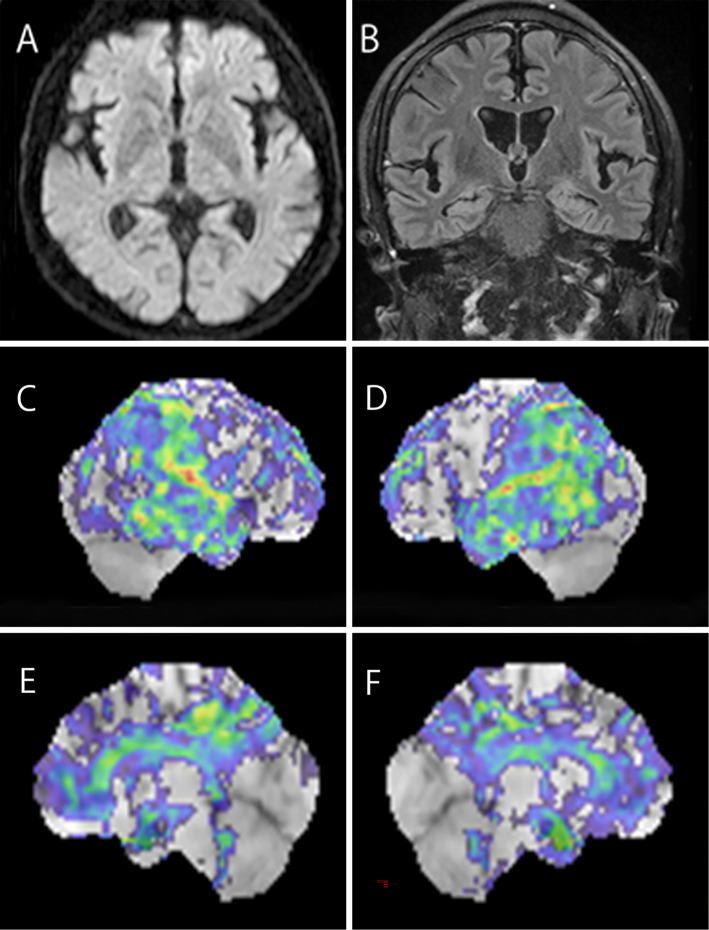

A 47-year-old man with a family history of juvenile dementia in his mother presented with memory loss and cognitive decline. Neuropsychological tests revealed impaired orientation, working memory, and apraxia. Magnetic resonance imaging revealed diffuse brain atrophy, and fluorodeoxyglucose positron emission tomography (PET) showed hypometabolism in the bilateral parietal lobes, posterior cingulate gyri, and precuneus, suggestive of Alzheimer's disease. However, amyloid-beta and tau PET scans were negative. Genetic testing revealed an abnormal repeat insertion in the prion protein gene, confirming inherited prion disease. This case highlights the need to consider inherited prion disease in the differential diagnosis of early-onset familial dementia.

Abstract Image